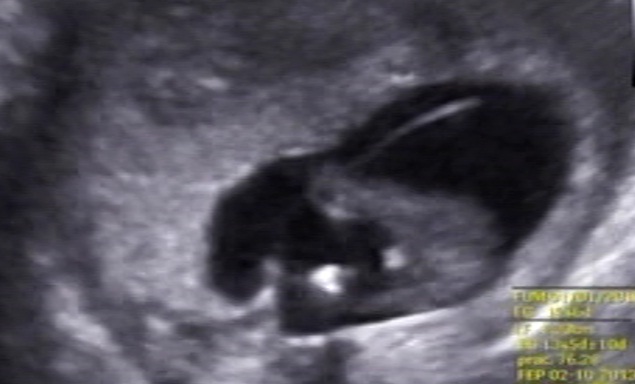

Boy or girl? 14 weeks.

Would you guess boy or girl? Could the white in the first pic be boy parts?

They are from a 14 week scan. Im having an other scan soon but im soo curios and would like to know what to expect when I go to that scan.

It seems to have something between the legs. My guess is a boy, hope this is what you want

Looks like there is something between the legs I would say boy.